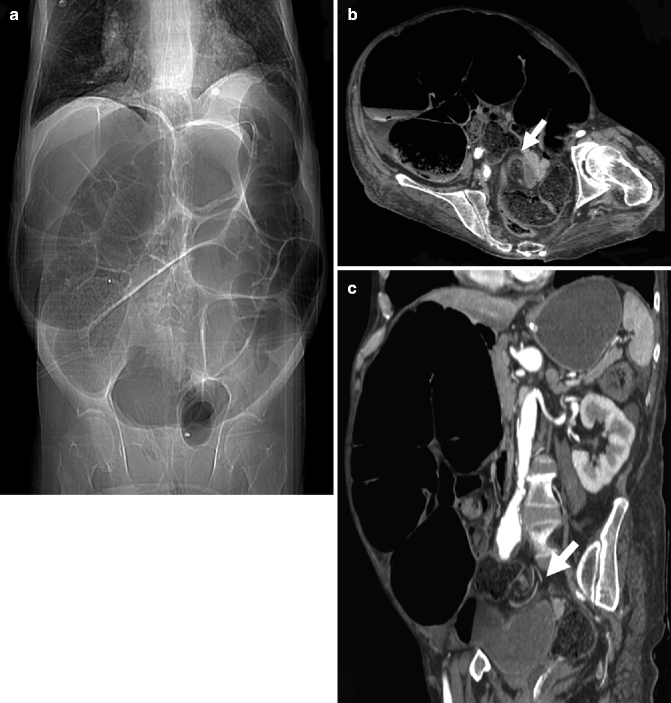

LargeBowel Obstruction in the Adult Classic Radiographic and CT Picture Frame Appearance Large Bowel Obstruction This is an important sign to appreciate, as it is indicative of a mechanical large bowel obstruction. This condition requires prompt diagnosis and treatment. A combination of the clinical and laboratory findings and ct scanning of the abdomen that demonstrates the underlying pathology should differentiate localized ileus from small bowel. If the cause of the obstruction is in the lumen. Picture Frame Appearance Large Bowel Obstruction.